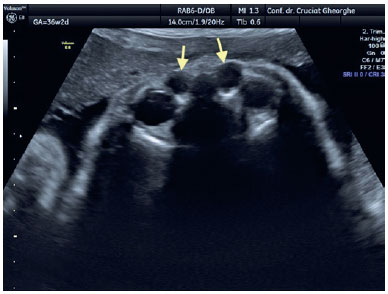

Examination of the fetal cephalic pole using fetal ultrasound performed at 31 WG revealed the presence of a 3-mm, liquid-filled, hypoechoic cyst located inferiorly and separated from the right eye ball (Figure 1). At 33 WG, the cystic lesion had enlarged (6/4.5 mm); however, it remained well demarcated from the eye ball and the nasal fossa. At the 36 WG follow-up examination, the dimensions of the right cyst were 8/7 mm and a similar lesion of 6/4.5 mm was identified contralaterally (Figure 2). At 38 WG, the DCC on the left side diminished and its content became more dense/opaque, whereas the structure on the right side maintained its liquid content and increased in size to 8/8.5 mm (Figure 3). All ultrasound examinations were performed using a Voluson E8 ultrasound system (GE Medical Systems, Zipf, Austria). Elective Cesarean section was performed at 39 WG, without perioperative complications. The newborn weighed 3,800 g, with an Apgar score of 10.